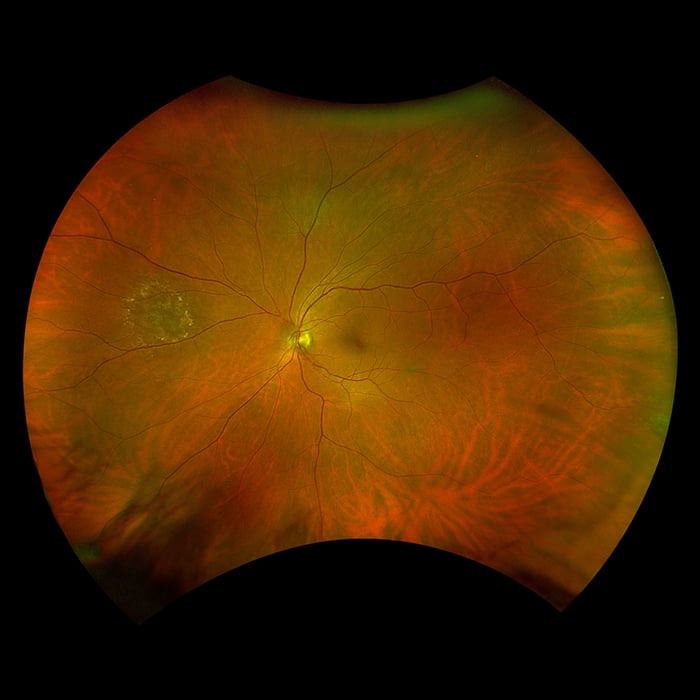

Daytona produces a 200° single shot optomap retinal image of unrivaled clarity in less than ½ second. This fast, easy, patient friendly, ultra-widefield imaging technology was designed for healthy eye screening and has been shown to improve practice flow and patient engagement.

Daytona provides eyecare professionals with UWF digital images of 200 degrees or up to 82% of the retina in a single, non-contact optomap image. In addition, the Daytona device comes with the OptosAdvance™ browser-based image review software, which allows for simple documentation, monitoring and referral processing to assist in patient management and improved patient flow.

optomap color rg (red and green laser) |